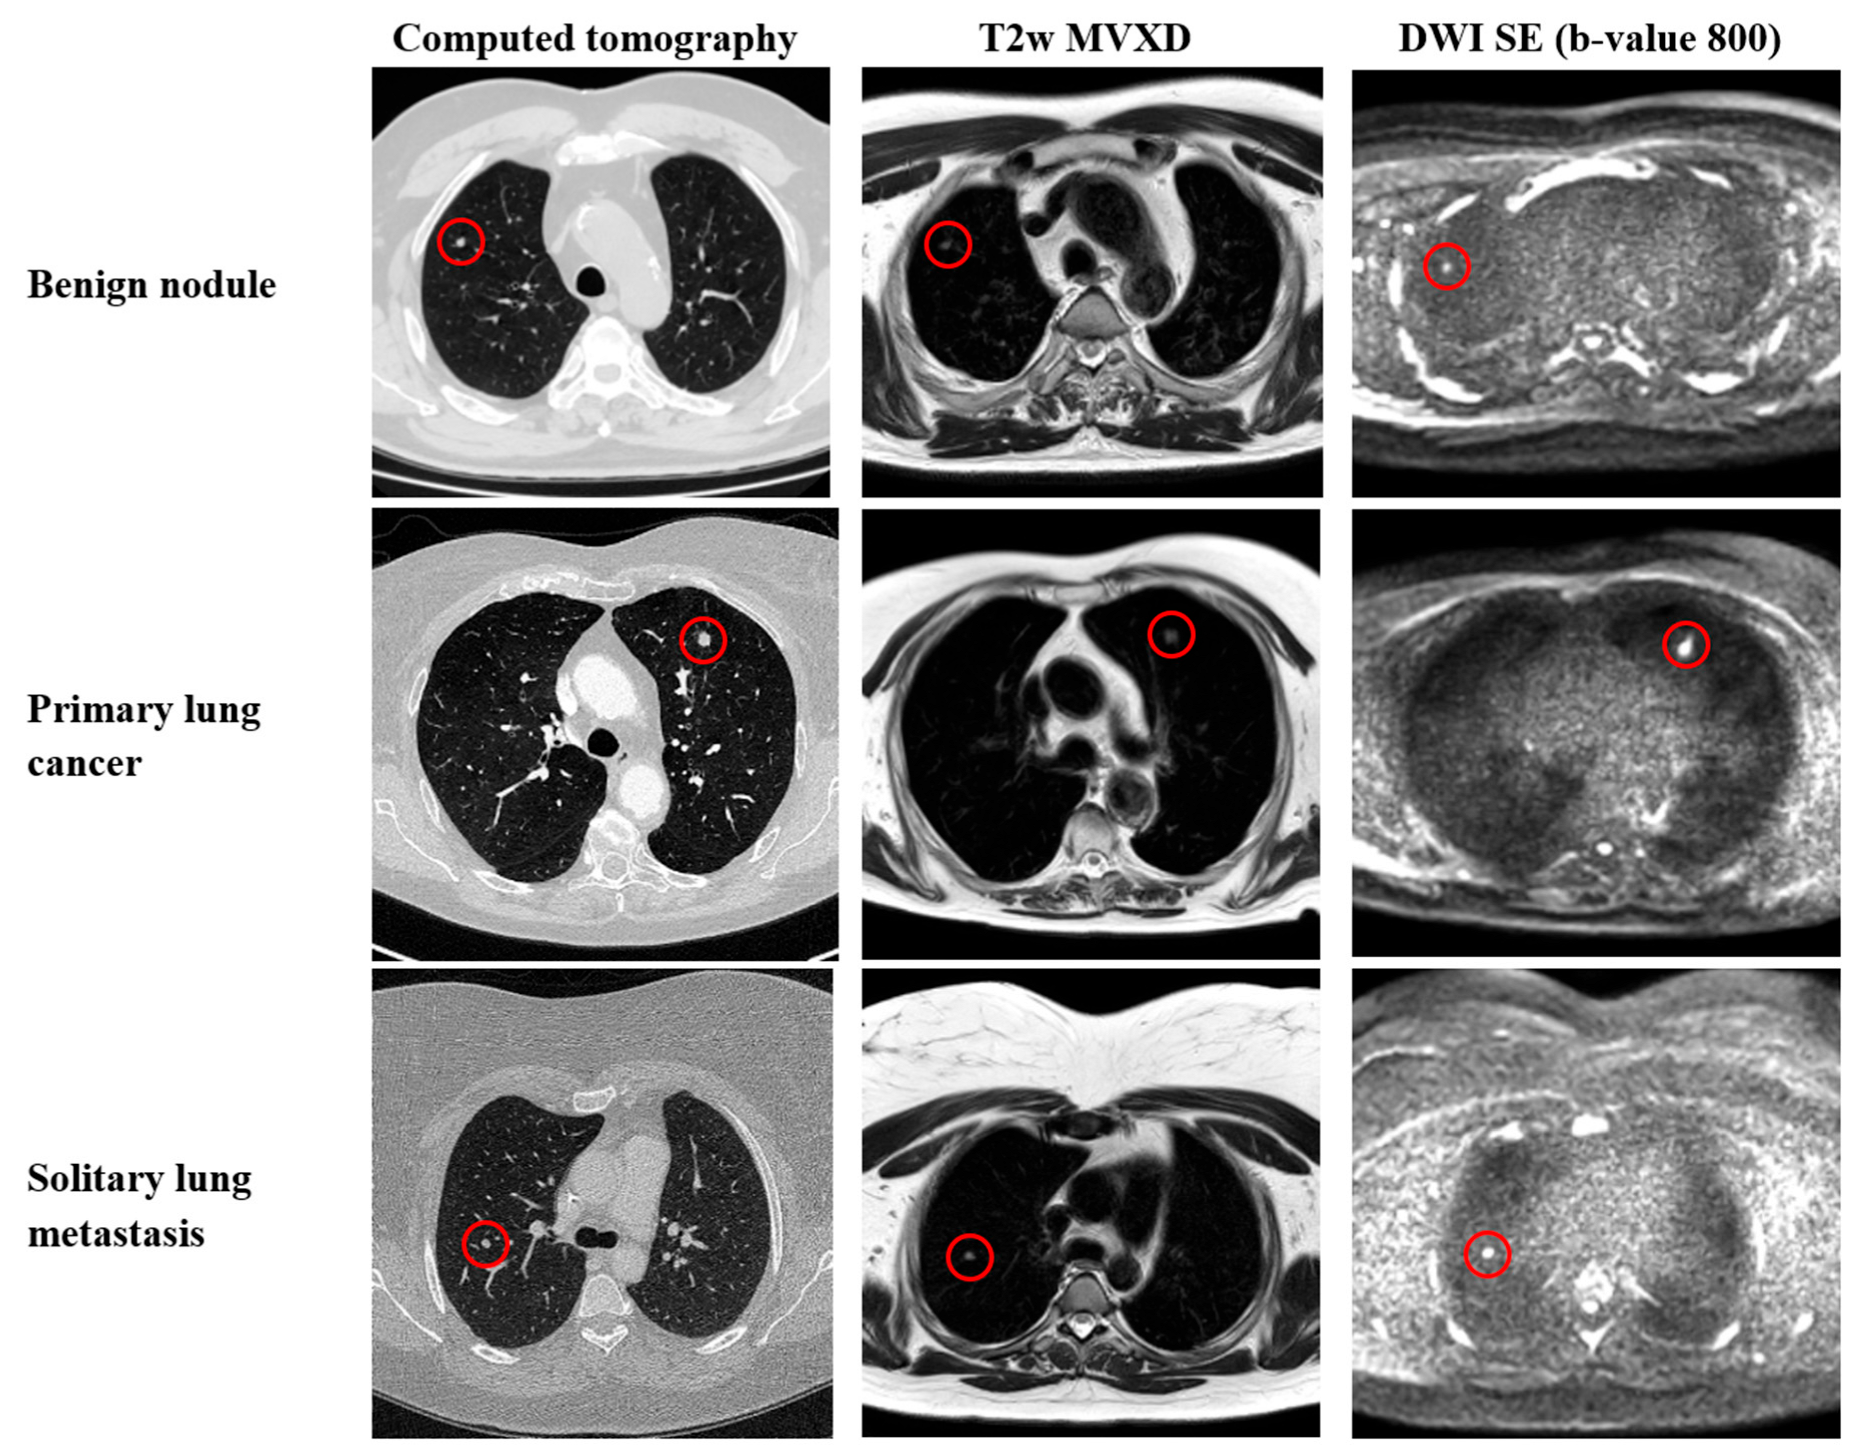

| Histological typing, no. (%) | |

| Benign nodule | 26 (39) |

| Primary lung cancer | 16 (24) |

| Solitary lung metastasis | 24 (36) |